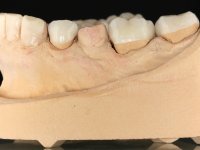

Realizado o diagnóstico e tomada a decisão quanto ao tratamento a executar, tornou-se importante definir qual a sequência de trabalho a adotar no sentido de conseguir a reabilitação da D.V.O. (V.D.O), de forma progressiva e equilibrada. Na primeira fase fez-se uma pré-impressão da arcada inferior com silicone tipo “putty” e em seguida realizou-se o preparo dentário de todo o sector posterior. O preparo para os overlays foi feito coronalmente à linha amelo cementaria no sentido de ser o mais conservador possível. A impressão foi feita com técnica de dupla mistura após afastamento gengival realizado com pasta de caulino. A provisória foi realizada com resina composta de polimerização dual. Em laboratório foram realizados os overlays após se ter aberto ligeiramente (1,5mm) a D.V.O. nos modelos montados em articulador semi-ajustável. Simultaneamente o sector antero-inferior foi encerado no sentido de acompanhar este aumento da D.V.O. Também foi confecionada uma chave de silicone translucido para posterior confeção dos provisórios antero-inferiores. Em boca foi primeiro realizada a provisionalização dos dentes anteriores utilizando resina composta previamente aquecida após preparação das superfícies dentárias para a adesão. Foi colocado o dique de borracha para promover o isolamento absoluto e posteriormente foram colados os overlays. Em laboratório foi realizada nova chave de silicone para confecionar os provisórios antero-superiores. Seguidamente em boca foram preparados os seis dentes antero-superiores após colocação do fio de afastamento gengival. Feita a preparação adequada das superfícies dentárias foi realizada a impressão com técnica de dupla mistura e a respetiva provisória. Em laboratório foram confecionadas 6 facetas feldespáticas num modelo de trabalho tipo “Geller”. A provisória foi removida e as facetas foram coladas em boca utilizando um isolamento relativo competente. Esta opção foi tomada em virtude de uma prévia experiencia negativa com a colocação do dique de borracha na mandibula. Após a colagem dos laminados antero-superiores foram dadas 12 semanas para avaliar a adaptação do paciente à nova situação e então iniciar a confeção das facetas antero-inferiores. Após colocação do fio de afastamento gengival. foram feitos os preparos dentários adequados e em seguida foi feita a impressão. Também foi feita a preparação do dente 3.4 que, entretanto, tinha sofrido uma fratura do overlay. As facetas e a restauração do 3.4 foram realizadas num modelo de trabalho tipo “Geller”. Após remoção da provisória, as facetas foram coladas em boca, utilizando um isolamento relativo pelas razões apontadas anteriormente. Após colocação do trabalho o paciente foi reabilitado por outros colegas com um implante na zona do 2.6 e substituição da coroa aparafusada sobre o implante colocado no local do 3.5. Posteriormente surgiram fraturas nos overlays dos dentes 4.7 e 3.7 que foram reabilitados com overlays em Zr.